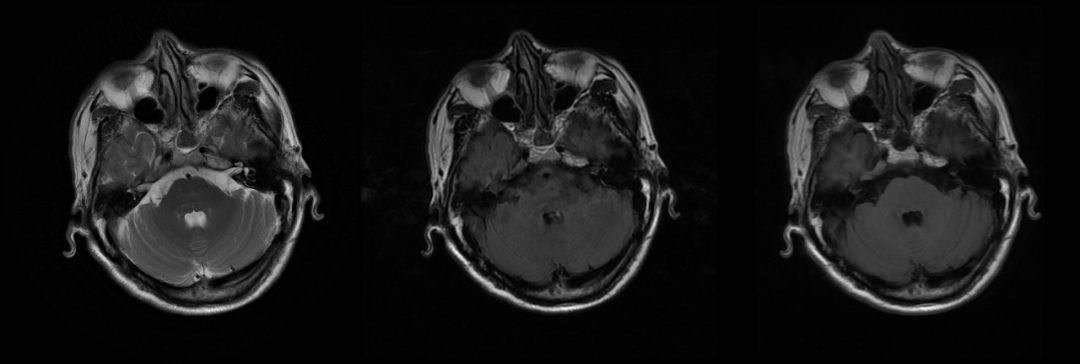

Case1:女,66 岁,3 个月前因间断意识不清就诊于我院,明确诊断为「原发性胆汁性肝硬化 失代偿期、肝性脑病」,给予保肝、降黄、抗感染、对症支持治疗后好转出院。近 2 周内患者出现嗜睡,间断意识不清。血钠 137 mmol/L。

Case2:男,60 岁,发现乙肝病原学阳性 25 年,黑便 1 天,伴有头晕、恶心、乏力,血钠 135.8 mmol/L。

Case3:男,56 岁,因「阵发性耳鸣 15 天,头晕、视物模糊 6.5 天。入院前 15 天出现阵发性耳鸣,性质如鸣笛音,持续约数秒,发作频率大约 1-2 次/天,入院前 6.5 天无明显诱因出现头晕、视物模糊,表现为头重脚轻感,走路不稳,无天旋地转感。既往:2 个月前出现过 3 次头晕,当时伴有视物旋转感。饮酒 30 余年,以前 7-8 两/天。